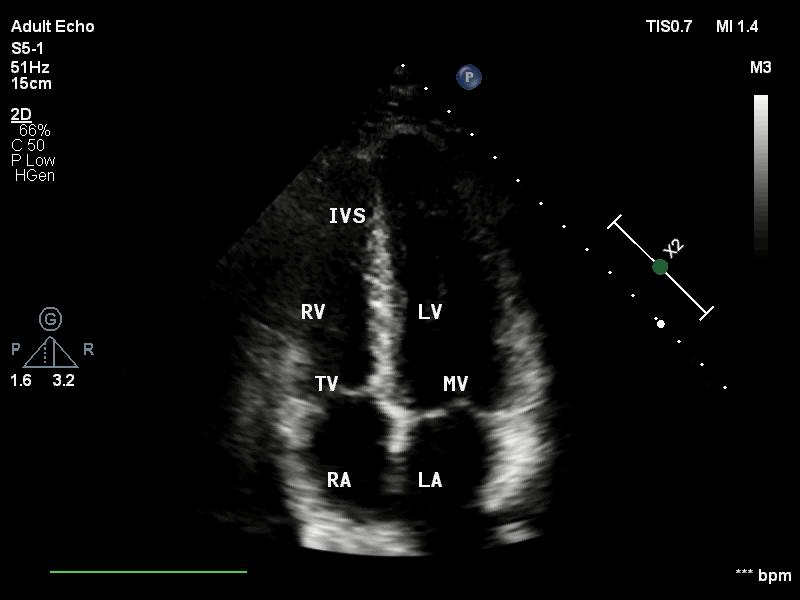

心尖三腔心切面二维超声2.3心尖四腔心切面

心尖四腔心切面二维超声心尖四腔心切面二维超声

LA:左房 LV:左室 RA:右房 RA:右室;

MV:二尖瓣 TV:三尖瓣 AV:主动脉瓣;

AO:主动脉 LVOT:左室流出道;

IVS:室间隔。